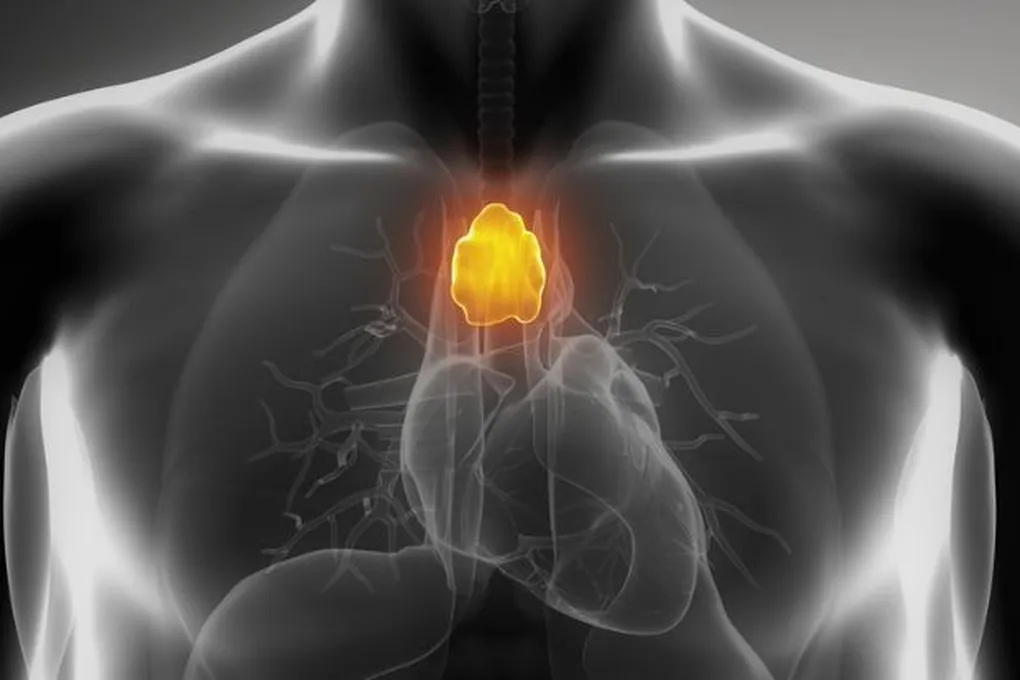

Что такое вилочковая железа

Всем известно, что в детстве тимус — настоящая «школа» для иммунитета. Именно здесь созревают Т-лимфоциты — те самые клетки-защитники, которые борются с инфекциями и болезнями. Если железу удалить в молодом возрасте, количество и разнообразие этих клеток остаётся сниженным на всю жизнь.

- Дети без тимуса даже хуже реагируют на прививки — их иммунная система просто не может правильно «запомнить» врага. Считалось, что к половозрелому возрасту железа «выполняет свою миссию», сморщивается и становится почти бесполезной. Её даже начали иногда удалять «заодно» во время операций на сердце — она ведь мешает хирургу, верно? Но так ли это на самом деле?

Учёные предполагают, что отсутствие тимуса нарушает тонкую настройку иммунной системы у взрослых. У части прооперированных пациентов в крови обнаружили меньшее разнообразие Т-клеточных рецепторов — а это прямой путь к снижению противоопухолевого надзора и развитию аутоиммунных сбоев.

- «Полученные данные убедительно свидетельствуют: тимус продолжает работать и во взрослом возрасте, производя новые Т-клетки и поддерживая наше здоровье», — делают вывод авторы работы. Получается, эта маленькая железа — не атавизм, а наш пожизненный союзник. Стоит ли так легко с ним расставаться?